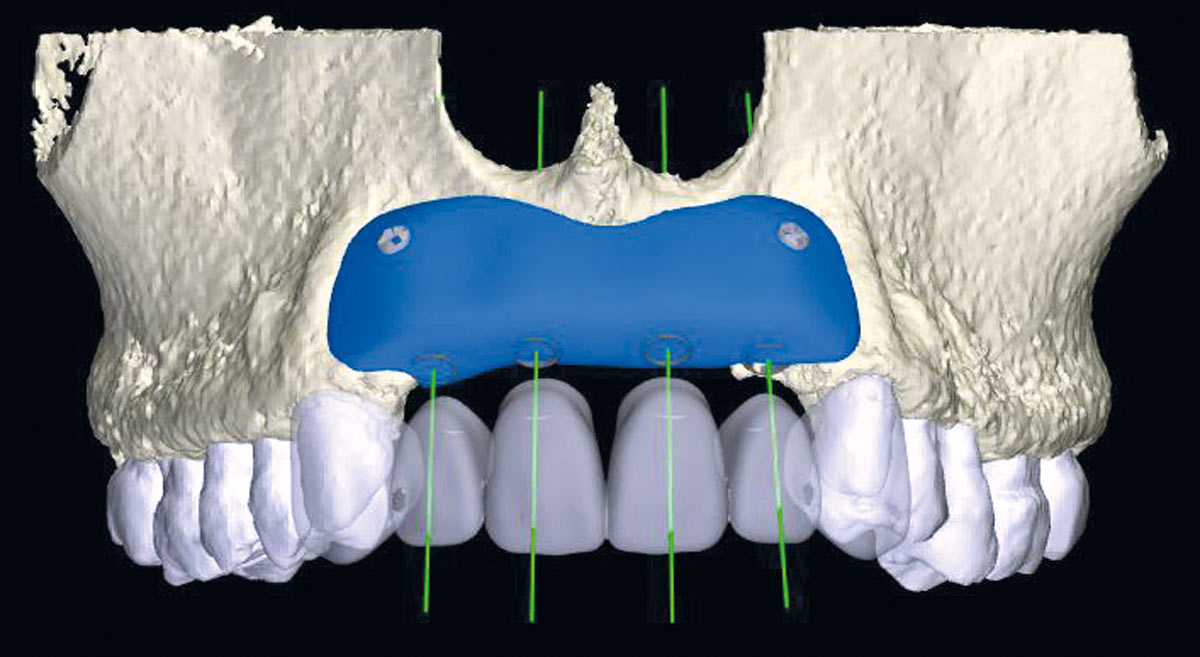

5/17 - Virtual three-dimensional reconstruction of the defect and bone block designRestoration of all four incisors with maxgraft® bonebuilder - Dr. Dr. Dr. O. Blume